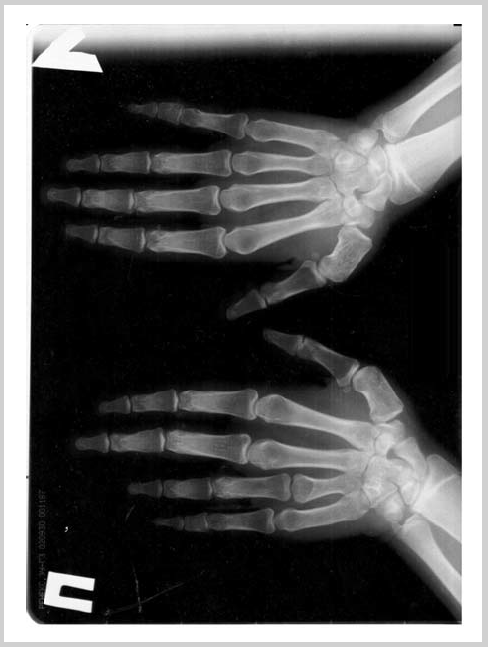

В Институте детской эндокринологии в возрасте 13,5 лет выявлены характерные для фенотипа Олбрайта признаки — задержка роста (SDS роста: –2,1), брахидактилия, умственная отсталость. Обращало на себя внимание наличие необычного кальцината: по ходу портняжной мышцы правого бедра плотное образование длиной 7 см шириной 4 см (рис. 9) — несколько нетипично для кальцинатов при НОО глубокое расположение (по ходу мышечной фасции). Ожирения и гипогонадизма у ребенка не было. Наряду с гипокальциемией (кальций ион. 0,85 ммоль/л) и гиперфосфатемией (2,68 ммоль/л) определялась резко повышенная концентрация ПТГ (466 пг/мл), субклинический гипотиреоз (ТТГ 4,46 мМЕ/л, Т4св 14,8 пмоль/л). Рентгенография кистей и стоп подтвердила наличие брахидактилии: укорочение диафизов пястных костей IV, V пальцев кистей, плюсневых костей IV, V пальцев стоп. Кроме того, отмечалось обызвествление стенок сосудов мягких тканей. С целью диагностики осложнений гипокальциемии было проведено КТ головного мозга, выявлен синдром Фара. Назначена терапия препаратами альфакальцидола (6 мкг/сут), кальция (2000 мг/сут), L-тироксином (50 мкг/сут), на фоне которой отмечалась нормализация концентрации кальция в крови и ТТГ. Молекулярно-генетическое исследование выявило мутацию в гене GNAS c.565_568delGACT p.M189fsX202. Наличие признаков НОО и выявленная мутация позволяют диагностировать ПГП Ia.

Среди наших пациентов брахидактилия встречалась у 16 пациентов в различной комбинации с другими проявлениями НОО. Брахидактилия при ПГП формируется за счет укорочения, как правило, IV и V пястных и плюсневых костей. Удостовериться в том, что укорочение пальцев происходит из-за недоразвития именно пястных костей помогает простой способ: при сжатии руки в кулак очевидно отсутствие IV, V пястно-фаланговых суставов (рис. 10; рис 11, см. на цв. вклейке, дополнительный материал на сайте журнала). Gas играет важную роль в процессах роста костей (препятствует дифференцировке хондроцитов и преждевременному закрытию зон роста), и отражением ослабления ее активности является укорочение пястных и плюсневых костей, преждевременное закрытие эпифизов и как следствие — низкорослость [13, 14].

Рис. 10. Укорочение IV, V пястных костей, выраженное больше справа.